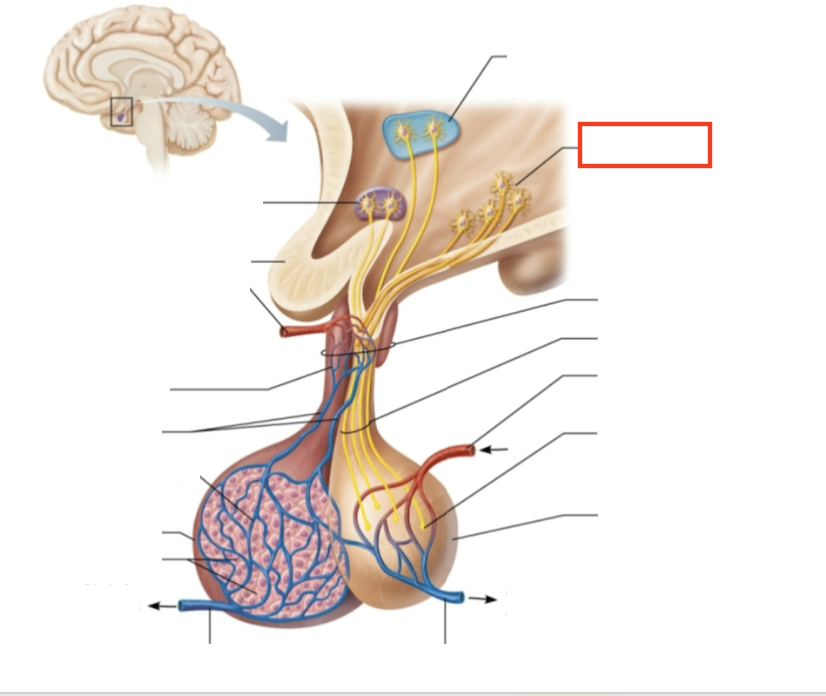

What structure is highlighted?

hypothalamic neurons in the paraventricular nuclei

What structure is highlighted?

neurons in the ventral hypothalamus

What structure is highlighted?

infundibulum (connecting stalk)

What structure is highlighted?

hypothalamic-hypophyseal tract

What structure is highlighted?

inferior hypophyseal artery

What structure is highlighted?

neurohypophysis (storage area for hypothalamic hormones)

What structure is highlighted?

posterior pituitary

What molecules are produced here?

oxytocin, ADH

What structure is highlighted?

venule

What structure is highlighted?

venule

What molecules are produced here?

TSH, FSH, LH, ACTH, GH, PRL

What structure is highlighted?

secretory cells of adenohypophysis

What structure is highlighted?

anterior pituitary

What structure is highlighted?

secondary capillary plexus

What structure is highlighted?

hypophyseal portal veins

What structure is highlighted?

primary capillary plexus

What structure is highlighted?

superior hypophyseal artery

What structure is highlighted?

superior hypophyseal artery

What structure is highlighted?

optic chiasma

What structure is highlighted?

hypothalamic neurons in the supraoptic nuclei